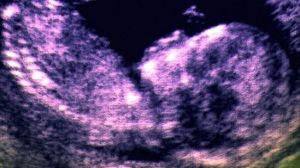

有科學家提出,可在嬰兒出生前就對其進行檢查,如有發現缺陷基因,立即進行修正,這種治療方法相比於產後或者嬰兒長大後再進行治療,優勢明顯。

這種產前基因療法存在不少優勢,例如,嬰兒出生後,因身體組織發育已經成形,再想對特定器官進行針對性治療,難度更大;因體型更小,處於子宮內的嬰兒所需基因載體量更少;因免疫系統仍處於初始階段,對基因載體產生免疫排斥反應的可能性也更低。

為了解決這個難題,有科學家提出可以從胎兒體內提取出細胞,在體外進行操作。科學家可將其中缺陷基因進行修正,然後再將經修正後的細胞植入胎兒體內,從而避開選擇基因載體這個難題。

不過,無論是採取哪種方式,首先都需要從胎兒體內提取出血液樣本,這么做無疑會增加胎兒流產幾率。不過,科學家同時也指出,同傳統的胎兒外科手術相比,產前基因療法已最大程度降低了胎兒流產的風險,而當前用於治療嬰兒出生缺陷的主流方法就是胎兒外科手術。